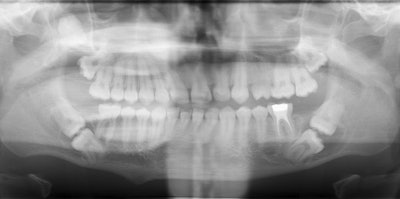

Additionally, the man's upper left second premolar was missing. A panoramic x-ray revealed bilateral kissing molars in his lower quadrants linked with cystic lesions encompassing the molar crowns. Also, it was noted that an ectopic upper right #8 tooth accompanied an associated mass in the right maxillary antrum. To determine the risks of surgically removing these teeth, the man was told to get a CBCT scan, the authors of the case report wrote.

The CBCT revealed the following features:

- A 17 mm vertical x 18 mm mediolateral x 24 mm anterior-posterior corticated soft-tissue mass in the right maxillary sinus, which was intimately involved with the displaced upper right tooth #8

- Thinning of the right maxillary sinus wall with a vertical dimension in excess of 28 mm and a mass involving the crowns of the upper right teeth #8 and #7

- The apices of the upper right tooth #8 were dilacerated and engaged the lateral wall of the right maxillary sinus

- The roots of the upper right tooth #7 engaged the floor of the maxillary sinus and the floor of the right nasal cavity, and the tooth's root was situated between the roots of the upper right #6 tooth

- The upper right tooth #6 had apical root resorption of the distobuccal root, blunting its palatal root

- The upper right tooth #5 was two rooted

- The upper left tooth #8 had dilacerated roots and engaged the floor of the left maxillary sinus

- The upper left tooth #4 was rotated

- The lower right teeth #6 and #7 showed a kissing molar arrangement with follicular expansion that measured up to 5 mm

- The roots of lower right tooth #7 displaced the right canal lingually

- Lower left teeth #7 and #8 showed a kissing molar arrangement with follicular expansion in a similar pattern to the contralateral side

- The right canal followed a lingual course through the mandible's ramus and ran lateral to and inferior to the expanded follicle before being displaced lingually by the crown and root structure of the lower right tooth #7

- The left canal followed a lingual course through the mandible's ramus before it was displaced interior by the follicle of the kissing molar, which then swung lingually, directly contacting with the roots of the lower left tooth #7 before rounding the apices to emerge as the left mental foramen

- The apices of lower left tooth #7 and lower right tooth #7 projected to the mental foramen